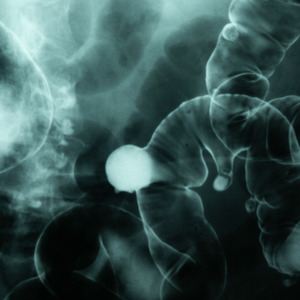

trávení

Žaludek si hýčkejte. Na co si dát pozor?

Svá střeva si hýčkejte, a to i přírodní cestou

Trpíte nadýmáním? Možná potřebujete léčit slinivku

Žaludeční vředy nejsou zrovna příjemné, přitom se stačí nepřecpávat